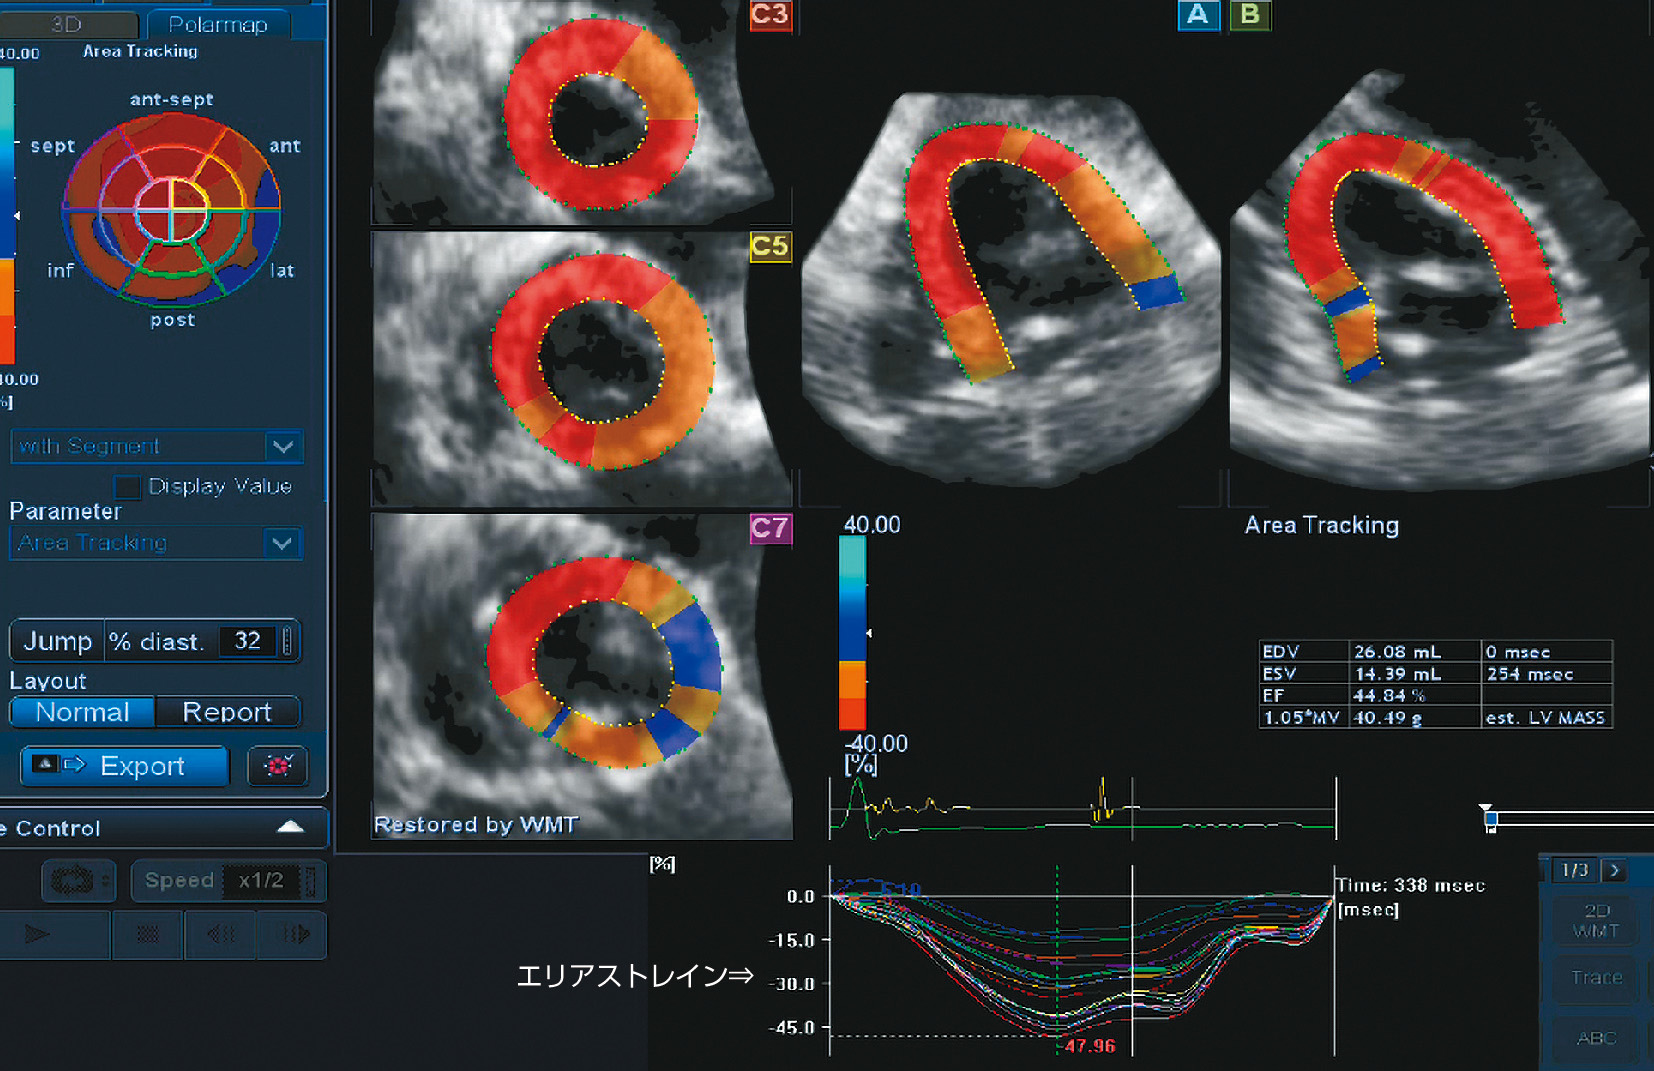

ⓔ図8-5-14 三次元スペックルトラッキング法により求めたエリアストレイン (イヌの心臓)